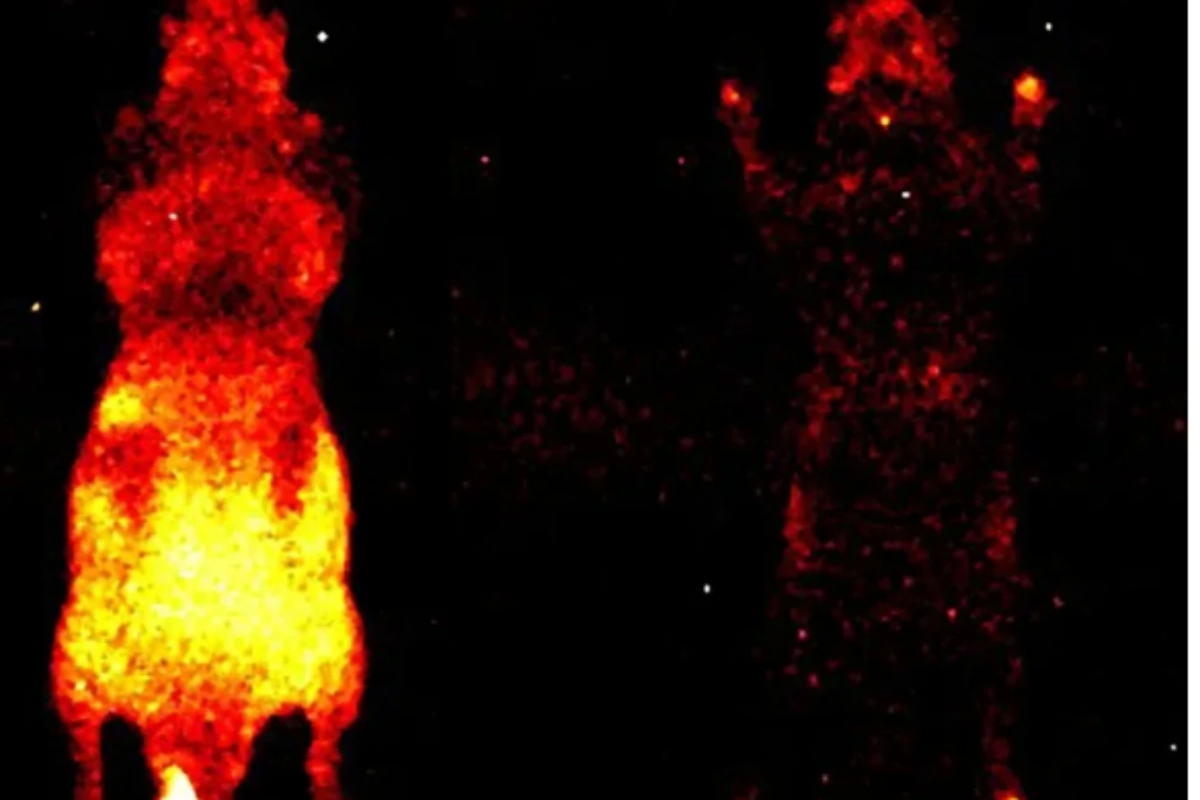

Əvvəlki tədqiqatlarda foton emissiyası yalnız ayrı-ayrı hüceyrələr səviyyəsində müşahidə olunmuşdu. Lakin Kalqari Universitetindən dosent Daniel Oblakın rəhbərlik etdiyi qrup bütün orqanizm səviyyəsində – həm canlı, həm də ölü vəziyyətdə – bu parıltını qeydə almağa nail olub.

Tədqiqat üçün siçanlar xüsusi qaranlıq kameraya yerləşdirilib və iki saatlıq eksperiment zamanı canlı heyvanların bədəni boyunca yayılan zəif işıq, baş, daxili orqanlar və pəncələrdə “isti nöqtələr” şəklində qeydə alınıb. Alimlər hesab edirlər ki, gələcəkdə bu zəif parıltının monitorinqi travmaların və müxtəlif xəstəliklərin erkən diaqnostikası üçün istifadə oluna bilər.